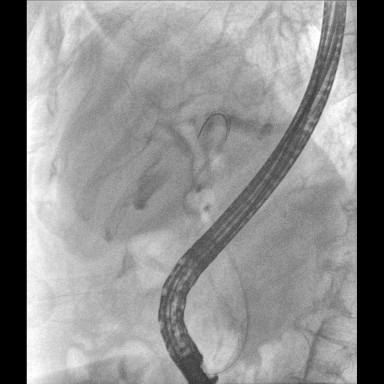

具備血管造影及數(shù)字減影(DSA)、路徑圖(Road-map)、透視、攝影等功能。 廣泛適用于介入科、血管外科、腫瘤科、消化內(nèi)科及骨科等多個(gè)臨床科室,典型應(yīng)用包括:TACE(肝腫瘤栓塞與化療灌注術(shù))、心臟起搏器置入術(shù)、四肢動(dòng)脈造影術(shù)、下肢靜脈濾器置入術(shù)、ERCP(經(jīng)內(nèi)鏡逆行胰膽管造影術(shù))等。

核心DSA軟件可實(shí)時(shí)生成高清血管影像,結(jié)合路徑圖功能,在手術(shù)中為醫(yī)生提供血管導(dǎo)航。

預(yù)留高壓注射器聯(lián)動(dòng)接口,C形臂開始透視時(shí),高壓注射器自動(dòng)注入造影劑,提高術(shù)中造影減影效率,減少醫(yī)師手推造影劑所受到的輻射暴露劑量。